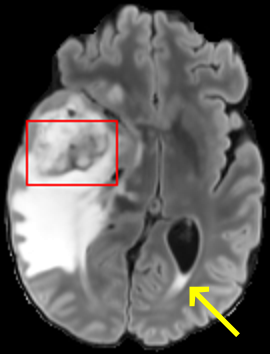

To test the impact of the iterative refinement on YODA’s translation quality, we compared regression and diffusion sampling on the RS data and present additional generation examples in Fig. 6. We observe that diffusion sampling visually resembles the appearance of the acquired images. Regression sampling preserves key anatomical features – the GM/WM boundary, WMHs (Fig. 4), the outline of the pallidum (Fig. 6) – but omits many high-frequency features. To investigate whether iterative refinement during diffusion sampling adds relevant and systematic medical information or only imitates acquisition noise, we performed ExpA sampling, i.e. averaging the output of several ( or ) diffusion trajectories. We observed a gradual loss of high-frequency details when increasing the (see also the supplementary video), indicating that the effect of the iterative refinement is non-systematic. For , the images are visually almost indistinguishable from the initial regression solution (see the supplementary video, and Fig.4 and 6). We directly compared the synthesis results of ExpA () and regression sampling quantitatively and found the differences to be minimal (SSIM: 99.73%, PSNR: 45.30 dB), i.e. diffusion sampling approaches the initial regression solution for a high . The quantitative analysis of the image quality (Tab. 1) showed that diffusion sampling impairs the assessed SSIM and PSNR in comparison to regression sampling for both the in- and external test sets, which we attribute to noise generation (Sec. 3.1). In turn, ExpA averages improved both metrics and, for , performed mostly on par with the regression solution in both test sets in terms of SSIM, while the PSNR in the RS was slightly increased (Tab. 1). However, we observed that ExpA sampling YODA improves the replication of systematic 3D low-frequency image intensity drifts (bias fields) due to the 3D synchronization in 2.5D diffusion sampling. Yet, this apparent advantage did not generalize to the external MBB dataset, as bias fields are MR protocol-specific.

We evaluated the impact of the proposed sampling methods on the performance of the independent, externally trained SHIVA-WMH tool as compared to manual reference labels (Tab. 1). Smoother images (higher or from regression sampling) yielded improved performance over those from diffusion sampling.

To assess the suitability of YODA-generated images for WMH detection independent of segmentation tools, we also calculated the CNR (15) of WMHs. This confirmed that the contrast of WMHs is preserved in the regression images, whereas we noted slightly reduced WMH contrast for diffusion and ExpA-sampled images (Tab. 1).

When analyzing the RS synthesis results (Fig. 4), we noted that most reference methods strive to imitate realistic images, but several artifacts can be observed such as hallucinated WMHs (SynDiff) and salt-and-pepper noise (SynDiff, I2I-Mamba, ResViT).